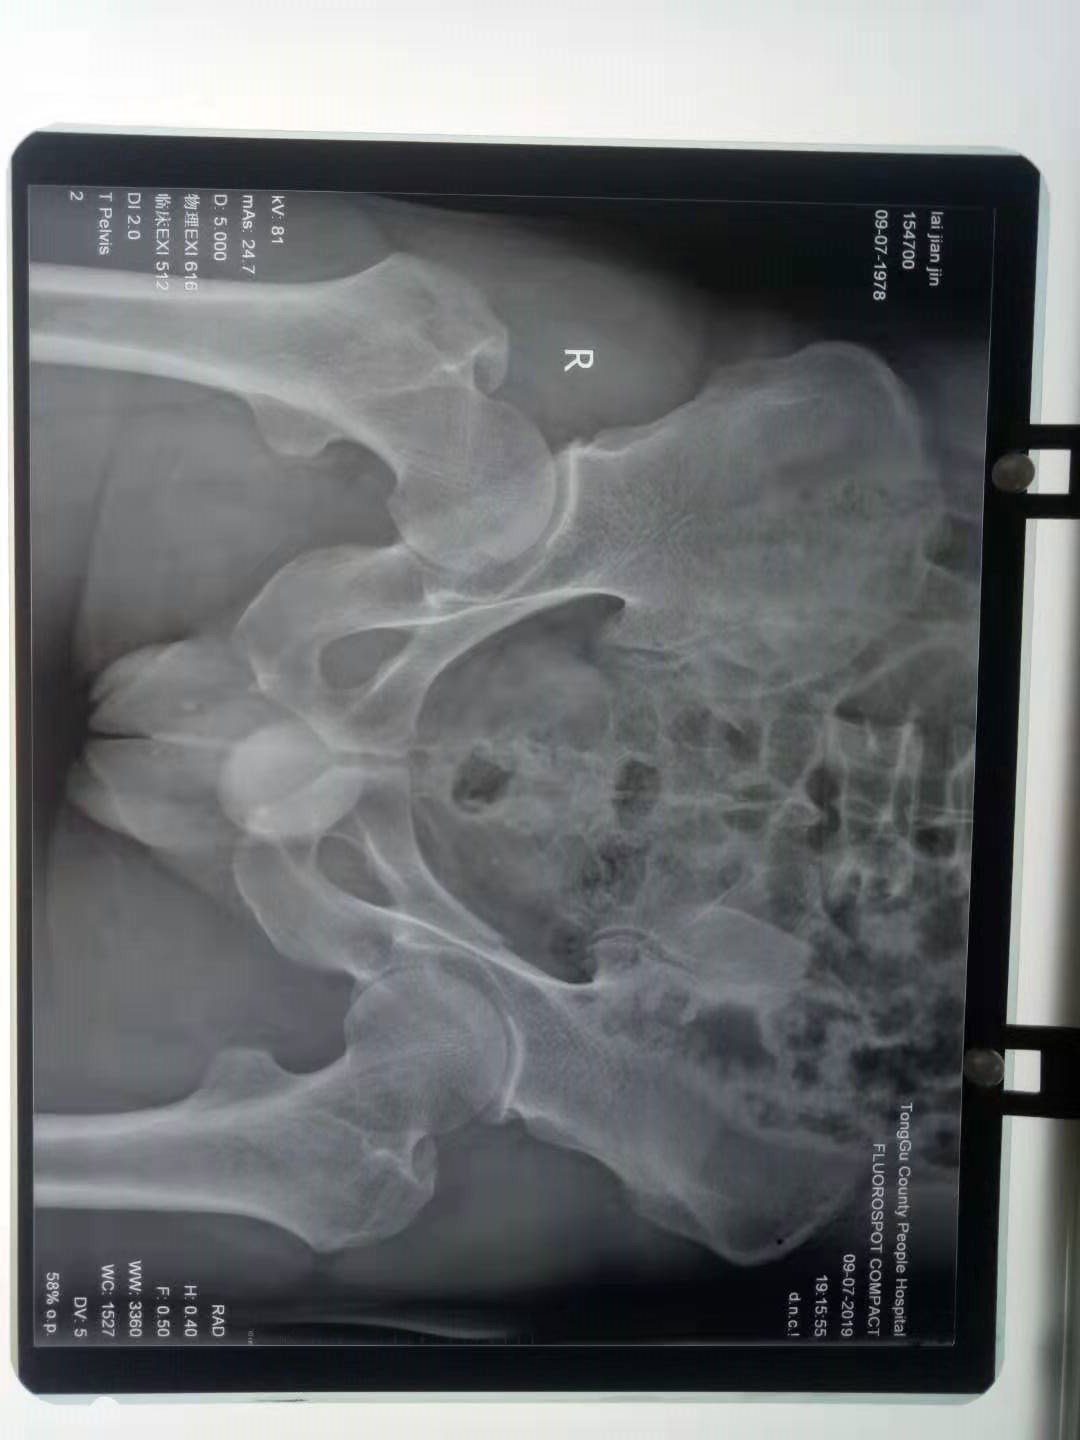

辅助检查:X线示:右尺桡骨远端粉碎性骨折,右侧肋骨骨折,左耻骨骨折,骨折端错位明显。

出院诊断:右尺桡骨远端粉碎性骨折,右侧肋骨骨折,左耻骨骨折,肺挫伤,右腕部软组织挫伤。

被鉴定人赖某某因高处摔下致尺桡骨远端粉碎性骨折,右侧肋骨骨折,左耻骨骨折,肺挫伤,右腕部软组织挫伤,经治疗康复后,右腕关节活动仍有功能障碍:掌屈40°,功能丧失30%;背屈30°,功能丧失40%;桡屈15°,功能丧失40%;尺屈40°,功能丧失20%;综合计算右腕关节功能丧失32.5%,参照2016年04月18日,最高人民法院、最高人民检察院、公安部、国家安全部和司法部联合发布的《人体损伤致残程度分级》第5.10.6脊柱、骨盆及四肢损伤11款{四肢任一关节(踝关节除外)功能丧失25%以上}规定;评定被鉴定人赖某某右腕的伤残程度为十级伤残。